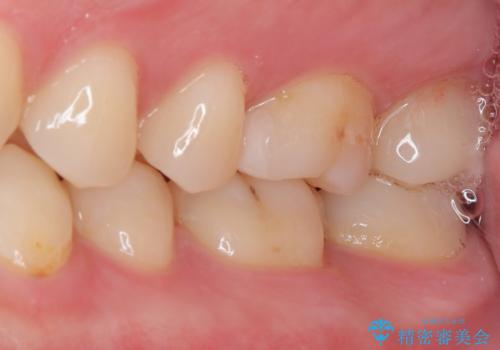

銀歯を気にせずに笑うことができると満足していただきました。